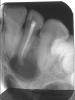

Alleghany Опубликовано 25 марта, 2011 Поделиться Опубликовано 25 марта, 2011 (изменено) Добрый день! Мне предстоит удалить радикулярную кисту на 2-м зубе. Вопрос к врачам: как бы вы посоветовали лечить? Удалять ли нерв в первом и/или третьем зубе? Можно ли вырезать, сохранив живыми 1-й и 3-й зуб? И еще вопрос: канал на снимке был запломбирован гуттаперчей специально под операцию и резекцию пару дней назад. Хирург в другой (платной) клинике говорит, что его не устраивает пломбировка и он хочет заполнять верхушку корня ретроградно дополнительно другим материалом. Есть ли в этом необходимость или он просто хочет взять побольше денег за ненужные по большому счету действия? Спасибо. Изменено 25 марта, 2011 пользователем Alleghany Ссылка на комментарий

Zborzh Опубликовано 25 марта, 2011 Поделиться Опубликовано 25 марта, 2011 Добрый день! Мне предстоит удалить радикулярную кисту на 2-м зубе. Вопрос к врачам: как бы вы посоветовали лечить? Удалять ли нерв в первом и/или третьем зубе? Можно ли вырезать, сохранив живыми 1-й и 3-й зуб? И еще вопрос: канал на снимке был запломбирован гуттаперчей специально под операцию и резекцию пару дней назад. Хирург в другой (платной) клинике говорит, что его не устраивает пломбировка и он хочет заполнять верхушку корня ретроградно дополнительно другим материалом. Есть ли в этом необходимость или он просто хочет взять побольше денег за ненужные по большому счету действия? Спасибо. По поводу депульпации соседних зубов - это вопрос правильного планирования операции . Обязательно надо сделать ЭОД соседних зубов ,если значения будут выше 15 - я бы рекомендовал еще до операции депульпировать соседние зубы , ибо , очень велика вероятность их затронуть при вылущивании кисты . Корневой канал запломбирован хорошо , ретроградной пломбировкой лучше не увлекаться (нет гарантии , что внесенный на культю зуба материал потом не отвалится ). После операции резекции я бы рекомендовал вам сделать вантовое шинирование ,т.е. пришинировать причинный зуб к рядом стоящим ,потому , как стабильность зуба в послеоперационном периоде - один из залогов успеха. Ссылка на комментарий

Zborzh Опубликовано 26 марта, 2011 Поделиться Опубликовано 26 марта, 2011 (изменено) можно и терапевтически попробывать полечить такой зуб если бы я делал резекцию, то тоже с ретроградным пломбированиема если прорут и отвалится (с чего бы вдруг) думаю не страшно ЭОД соседних зубов +1Как вы терапевтически такой зуб полечите ,если есть перфорация, тут и материал за верхушкой? Конечно , можно было бы пойти по пути введения гидроокиси кальция и наблюдения , но в данном клиническом примере , изначально решили пойти на РВК , я даже считаю , что правильно , только , с соседними зубами надо определиться. Изменено 26 марта, 2011 пользователем Zborzh Ссылка на комментарий

DShu Опубликовано 26 марта, 2011 Поделиться Опубликовано 26 марта, 2011 Как вы терапевтически такой зуб полечите ,если есть перфорация, тут и материал за верхушкой? не думаю, что это перфо Ссылка на комментарий

Zborzh Опубликовано 27 марта, 2011 Поделиться Опубликовано 27 марта, 2011 не думаю, что это перфоА что же это тогда ? =) Ссылка на комментарий

Хирург Опубликовано 30 марта, 2011 Поделиться Опубликовано 30 марта, 2011 не меньше года. резекция без ретроградной пломбировки - выброшенные на ветер деньги и зуб.Если канал перепломбирован перед операцией, то можно и без ретроградного пломбирования. Хотя возможно раздвоение канала у верхушки, тогда при отсутствии материала в ответвлении возможен рецидив. Соседние зубы я бы депульпировал, т.к они прилежат к кисте. Ссылка на комментарий